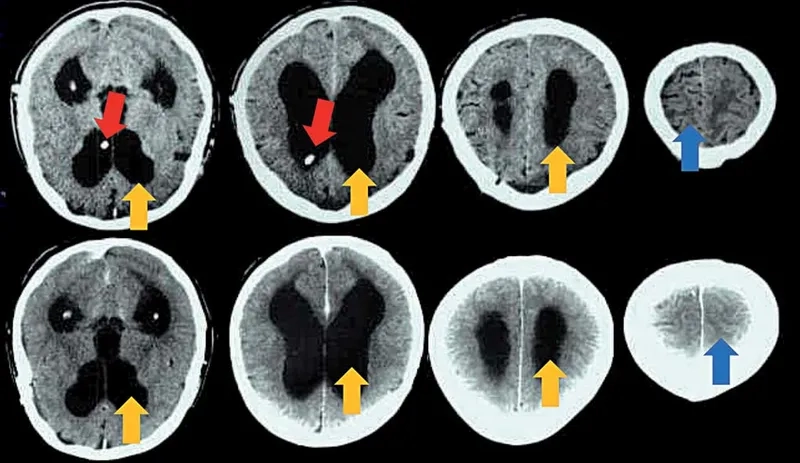

MRI brain scan showing enlarged ventricles in NPH